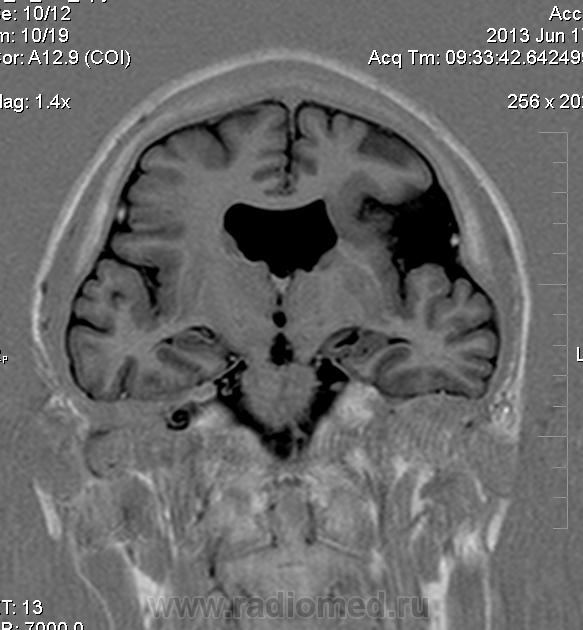

Мужчина 32 лет. Из анамнеза: перинатальное повреждение ЦНС, ДЦП, дизартрия, правосторонний верхний монопарез. С 16 лет приступы эпилепсии.

Аплазия прозрачной перегородки. Шизэнцефалия с открытыми краями в лобно-теменной области слева. Шизэнцефалия с закрытыми краями в лобной области справа? Утолщение коры по контуру расщелин и в области глазничной извилины правой лобной доли. Микрогирия? Гиперостоз костей свода черепа. Уважаемые коллеги, возможно я ошибаюсь, или есть еще аномалия?

сочетания отсутствия прозрачной перегородки и дисплазии ( разно степени выраженности) зрительных неровов  указывает на септоптическую дисплазию-нарушение развития в области средней линии , сопровождается мнггими другими структурными аномалиями, чаще шизэнцефалией.

Спасибо. Как тогда лучше сформулировать заключение? МР-картина кортикальной дисплазии : двусторнняя шизэнцефалия с утолщением коры по контуру расщелин, микрогирия в лобной области справа, очаг гетеротопии серого вещества в области  глазничной извилины правой лобной доли. Признаки септооптической дисплазии (гипоплазия зрительных нервов, аплазия прозрачной перегородки). Лиссэнцефалии не вижу. Есть сомнения по поводу шизэнцефалии справа (может быть я запуталась в микрогирии и мерещится шизэнцефалия?) Нет ли какой либо анамалии развития черепа?

На мой взгляд, полимикрогирия двусторонняя (конвекситальные отделы дорзальных отделов лобных долей и частично теменных, а также в базальном отделе полюса правой лобной доли) + закрытая шизенцефалия левой лобно-теменной области. Аплазия прозрачной перегородки (как признаки лобарной голопрозенцефалии).